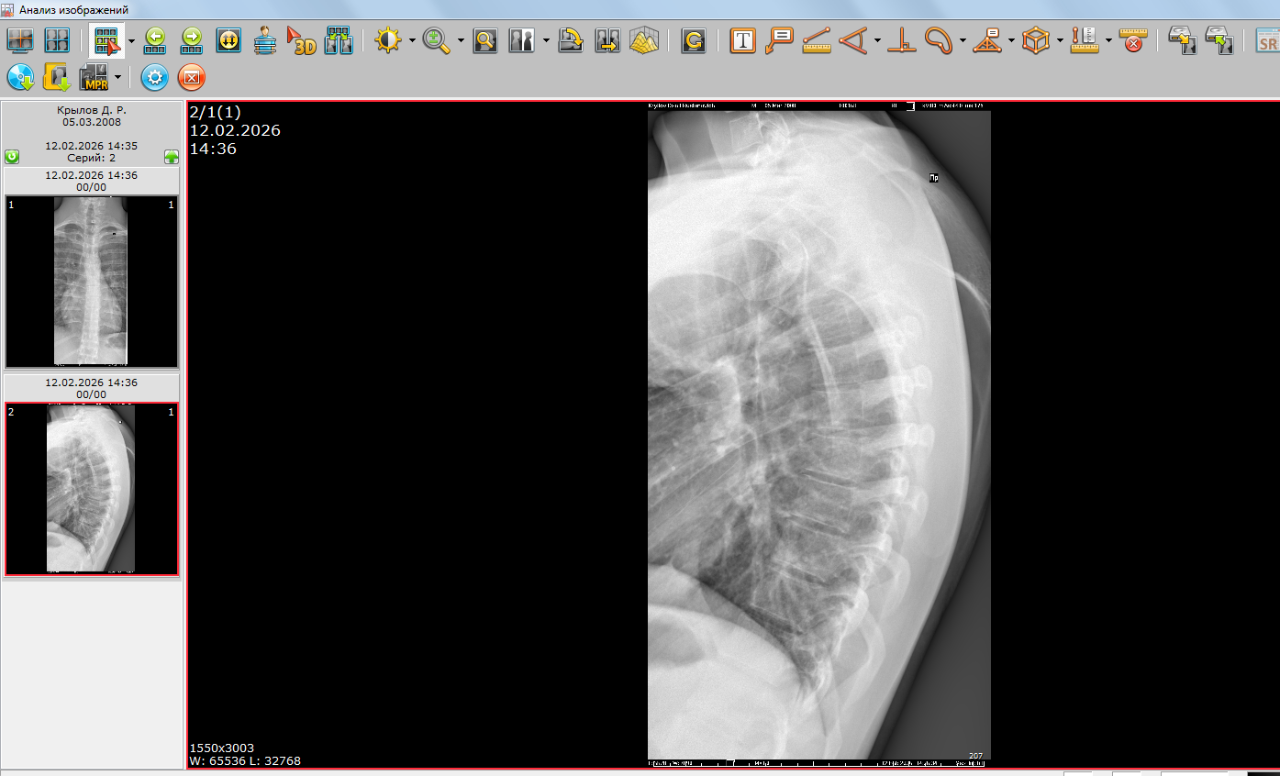

Открыты ли зоны роста на данных снимках

Здравствуйте, можно ли по данным снимкам определить открыты ли зоны роста? А также совпадает ли костный возраст с паспортным? Мой рост 174 см, Рост отца 176 см, рост мамы 158см. За год вырос на 3 см. Заранее спасибо.